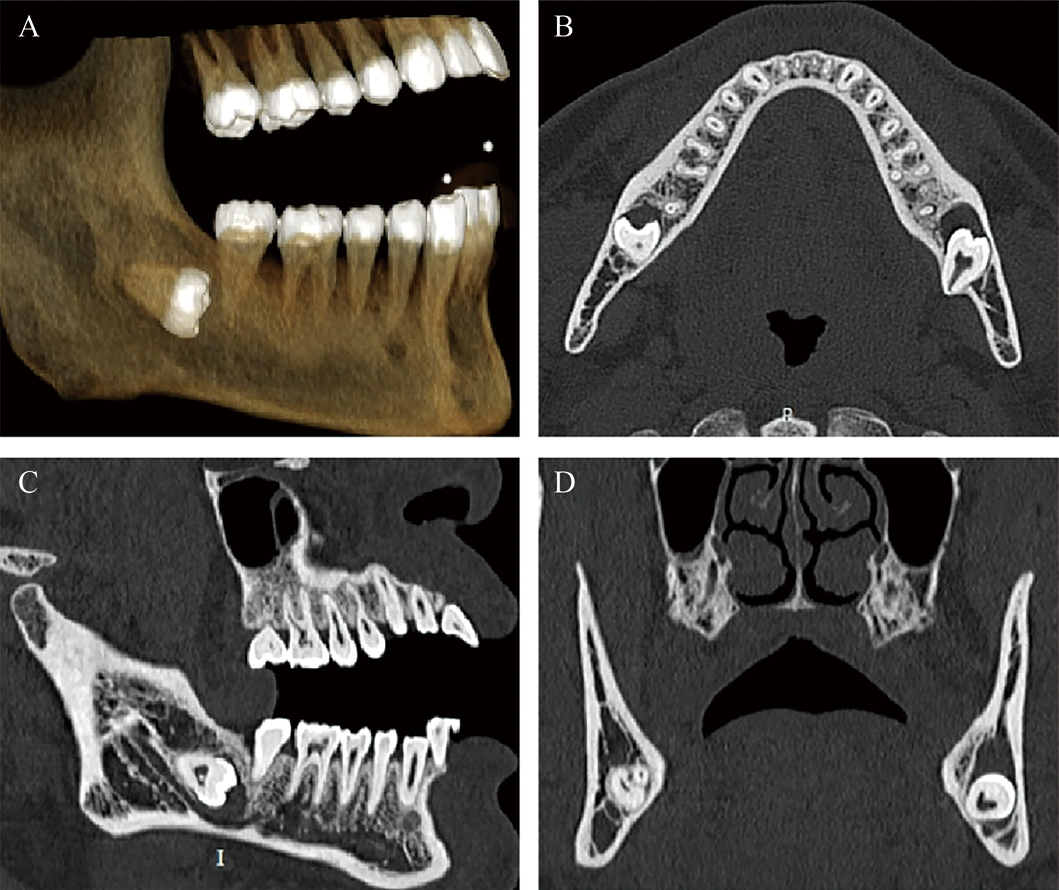

• 图2 下颌骨第三磨牙阻生伴囊性病变CT表现 A.三维重建图像;B.水平位图像;C.矢状位图像;D.冠状位图像。